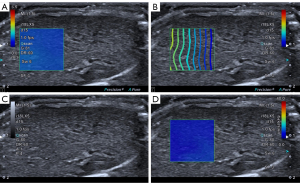

An experienced US abdominal sonographer examined each rat at specified times. The machine used for the experiment was an ultrasound scanner (Aplio i800; Canon Medical Systems Corporation, Otawara, Tochigi, Japan) equipped with a linear array transducer (18 MHz) and in accordance with guidelines proposed by the World Federation of Societies for Ultrasound in Medicine and Biology and the European Federation of Societies for Ultrasound in Medicine and Biology (28,29).

Before US exams, rats were anesthetized by intraperitoneal injection with a ketamine/xylazine mix (60 mg/kg ketamine, 7.5 mg/kg xylazine). During anesthesia, the needle was inserted into the lower abdomen far from the liver, and back extraction was performed before each injection to ensure that no abdominal organs or blood vessels were injured. The rats were placed on a heating pad in the supine position, and the abdomen was shaved to fully expose the abdominal skin and then coated with an adequate amount of ultrasonic couplants. The operator selected the ideal acoustic window in the abdominal region as much as possible without artifacts caused by ribs and gas. An approximately 1×1 cm sample box was placed roughly 1.0–1.3 cm beneath the capsule on a grayscale picture. The SWD ultrasound image was then activated, and the machine automatically displayed a twin view of the grayscale map and shear wave propagation map, after which it switched into quad-view mode, comprising 4 maps (SW speed map, propagation map, grayscale map, and SWD slope map). After cooling for 5 s to stabilize the SWD image, the image was captured and saved. Since each pair of photographs was interlocked, the SW speed and SWD slope values were obtained simultaneously by placing the region of interest (ROI) on the map. A 2 mm circular ROI was inserted in the liver parenchyma using the propagation map as a guide, avoiding major arteries and the transducer’s compression impact (Figure 1). A total of 15 measurements were obtained by measuring SW speed and SWD slope 3 times from 5 separate images to increase repeatability, and the mean value was selected for subsequent analysis. Two operators with more than 10 years of experience in abdominal US and more than 5 years of experience in elastography performed all SWD measurements independently. In addition, operator 1 performed a second measurement 30 minutes after the initial examination, and operator 2 performed the measurement in the same manner, with no regard to the measurement results of the first operator. The measurement results of operator 1 were used in subsequent statistical analyses.